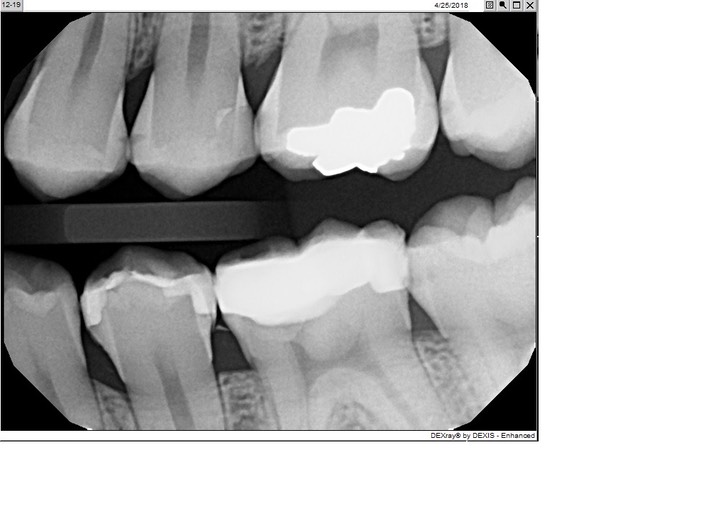

Kris Nip #19